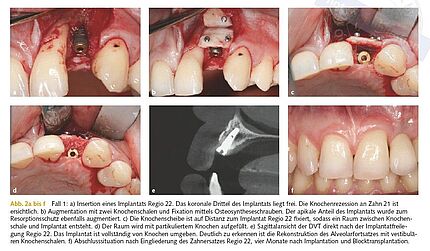

In den letzten Jahren ist eine Zunahme des Interesses an Knochenaugmentationen mit nicht erhaltungs- würdigen Zähnen erkennbar. Das Verwerfen von extrahierten Zähnen ist zurzeit noch tägliche Routine in Zahnarztpraxen und Kliniken. Dieser Fallbericht illustriert die Situation eines 62-jährigen Patienten, bei dem nach Entfernung der Oberkieferfrontzähne der Alveolarfortsatz einen komplexen knöchernen Defekt aufwies. Die Schaltlücke wurde zweizeitig rekonstruiert. Hierbei wurde der knöcherne Defekt mittels der Tooth Shell Technique nach Korsch unter Verwendung von autologem Dentin rekonstruiert und mit zwei Implantaten sowie Implantatkronen prothetisch versorgt. Abschließend erfolgte eine Transplantation von freier keratini-sierter Schleimhaut zur Rekonstruktion des Vestibulums und zur Stabilisierung der periimplantären Mukosa.

Zeitschrift: ZWP-Online – Implantologie Journal

Ausgabe: 05/2023

Autoren: Prof. Dr. Michael Korsch, M.A.,

Dr. Abdel-Karim Mamar

Der Fallbericht schildert die Situation eines SO-jährigen Patienten nach Zahnverlust regio 22. Die bukkale Knochenlamelle war infektionsbedingt weitestgehend resorbiert, wodurch sich die Notwendigkeit einer Augmentation im Zuge einer Implantation ergab. Da der Patient eine Knochenentnahme ablehnte, erfolgte eine laterale Kieferkammaugmentation mit autologem Dentin. Zum Einsatz kam dabei eine neue Methode: die sogenannte Tooth-shell-technique nach Korsch.

Zeitschrift: ZM – Zahnärztliche Mitteilungen

Ausgabe: 9/2022, Seiten 38 – 43

Autor: Prof. Dr. Michael Korsch, M.A.